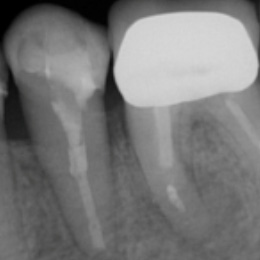

Fallbeispiel: Frontzahntraumata-Trauma im Alter von 9 Jahren mit Recall nach 22 Monaten

Frontzahntraumata sind im Kinder- und Jugendalter nicht selten. Bei noch nicht abgeschlossenem Wurzelwachstum können solche Zähne erfolgreich mit einer Revaskularisation behandelt und erhalten werden.